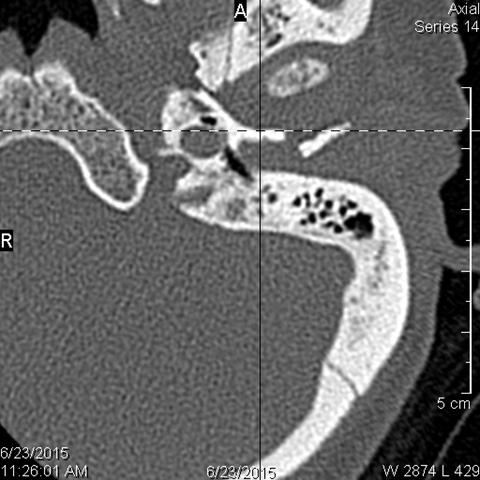

Right Temporal Bone

The external auditory canal shows abnormal soft tissue thickening.

The roof of the mastoid and/or middle ear is fractured.

A possible meningocele and/or encephalocele or CSF leak is present.

The ossicles, in particular the incus long process, the incudostapedial joint and stapes are fractured or dislocated.

The facial canal including the labyrinthine, tympanic and descending portions and nerve are fractured.

The inner ear including the lateral semicircular canals, vestibule and/or cochlea is fractured or otherwise abnormal.

There is subperiosteal, epidural or subdural hematoma along the roof of the mastoid or middle ear or the superior and posterior (intracranial) surfaces of the petrous portion of the temporal bone.